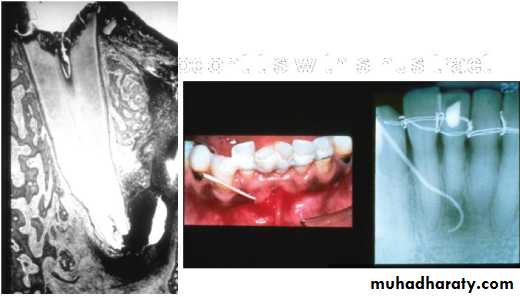

Gutta Percha POINT TRACING

Can localize the endodontic lesion to the specific tooth.Aids in the differential diagnosis between a periodontal and an endodontic lesion.

Placing a gutta percha point through the sinus/fistula tract and take a radiograph.